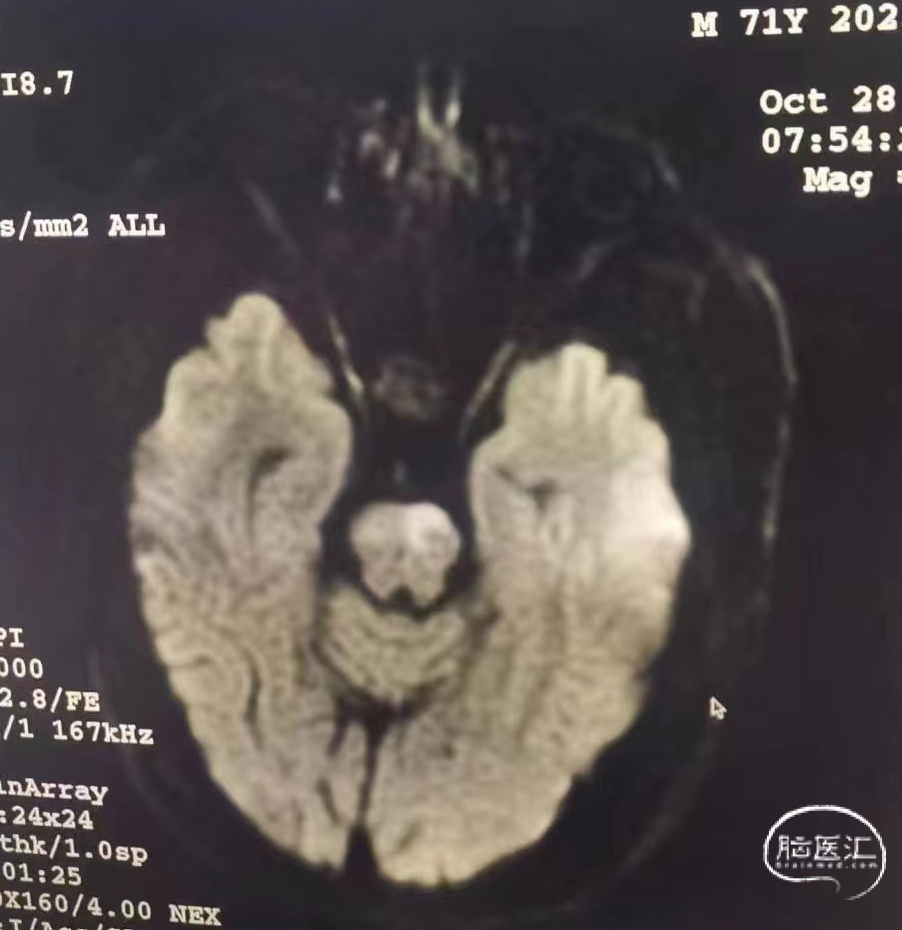

➢2023年10月28日

头颅MRI平扫:脑桥急性脑梗死,基底动脉近端重度狭窄。